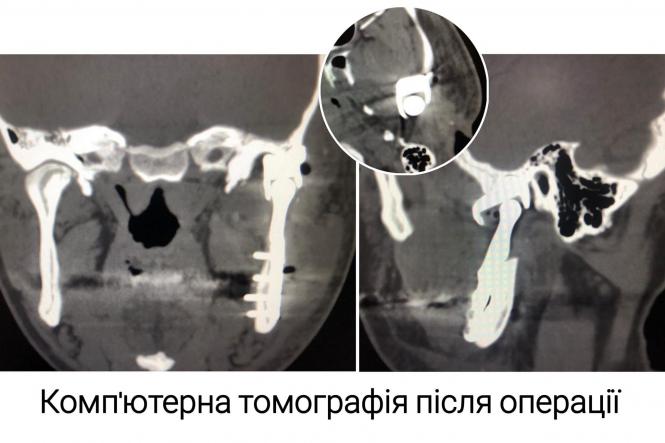

- Команда щелепно-лицевих хірургів лікарні Пирогова виконала високотехнологічну операцію заміни (ендопротезування) скроневонижньощелепного суглобу пацієнту після важкої травми обличчя.

Операція унікальна для Вінниччини. Її виконали з використанням сучасних біоінженерних технологій.

Індивідуалізований ендопротез для повної заміни скроневонижньощелепного суглобу був виготовлений комбіновано з медичного титану (Ti6Al4V Grade 23) та ультрависокомолекулярного поліетилену (UHMWPE).